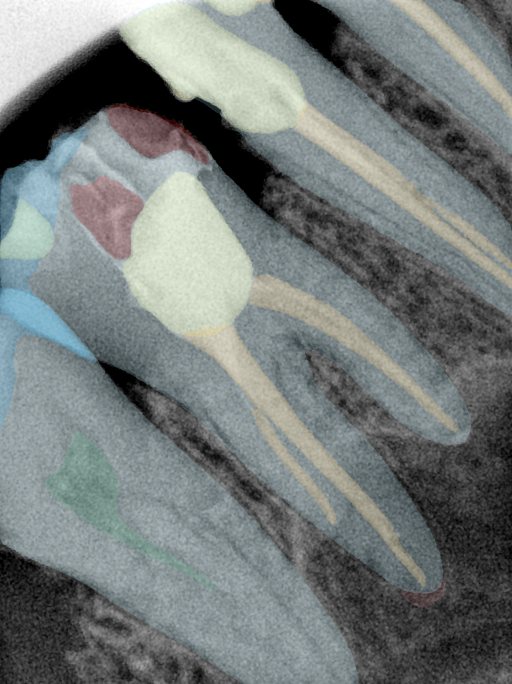

CR/DR 牙齿分割阶段记录

当前进展

- 完成了 CR/DR 牙齿相关分割训练

- 当前结果已经达到阶段预期,但仍有细节问题需要继续处理

相关测试

遇到的问题

- 训练过程中出现过 mask 下移问题

- 部分结果会出现 box 填充异常

- mask 边缘仍然有比较明显的锯齿感

参考